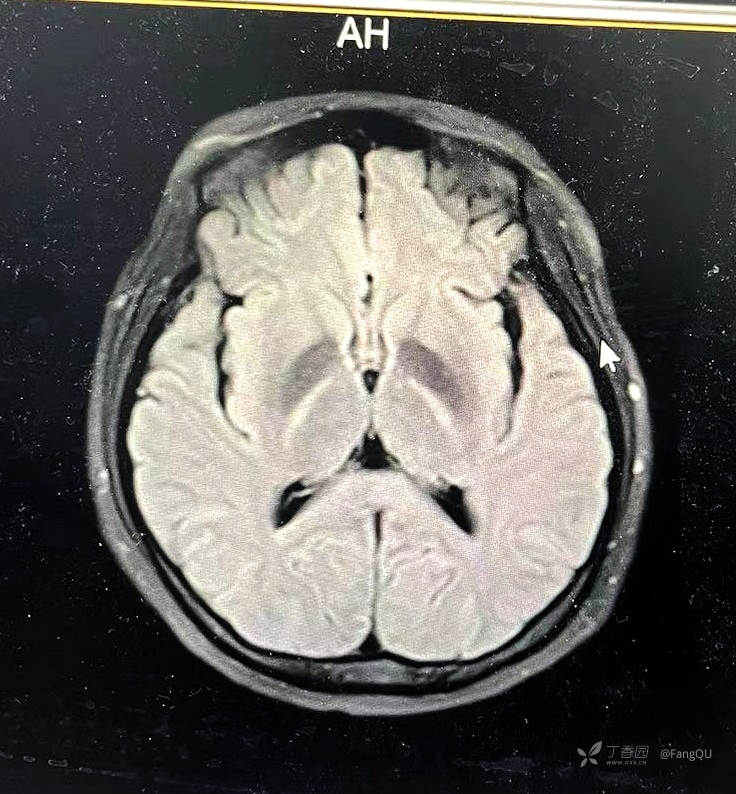

辅助检查:血气分析(入科当天):pH7.38,pCO2(30mmHg),pO2(104mmHg),Na+135mmol/L。头颅MR:室周、双侧内囊后肢、小脑中脚DWI高信号ADC低信号,影像见下。

初诊:毒性白质脑病,某物中毒?